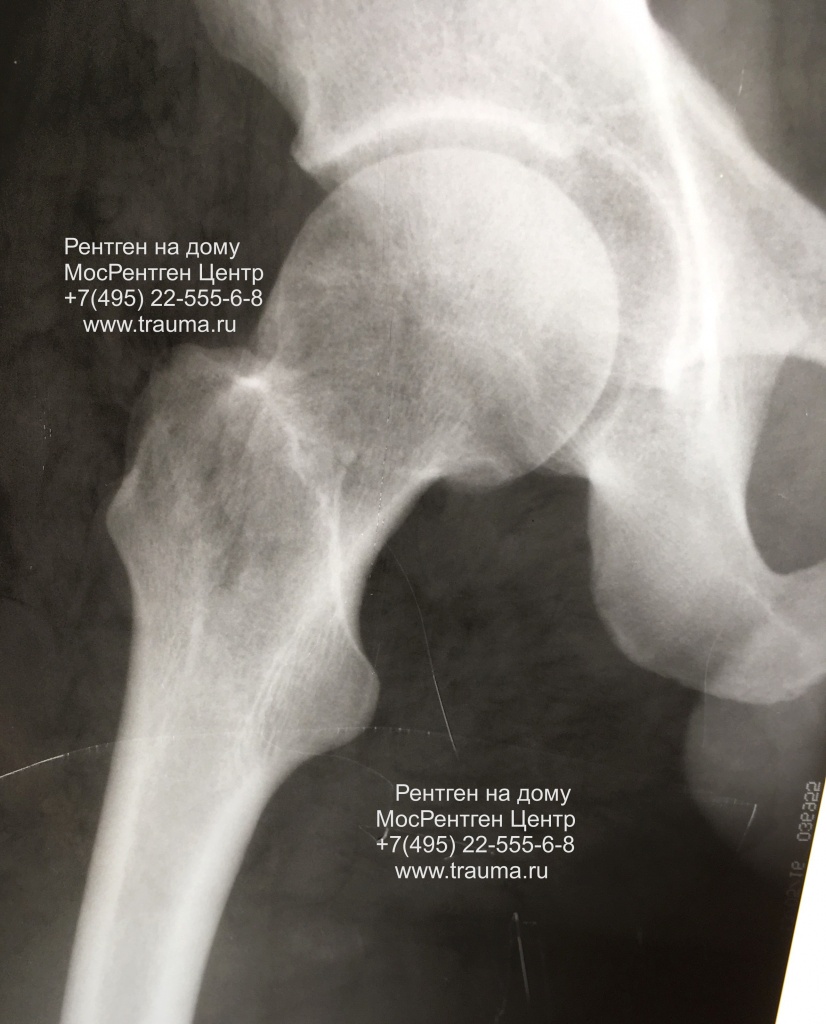

Рентгеновские снимки: Синовит тазобедренного сустава